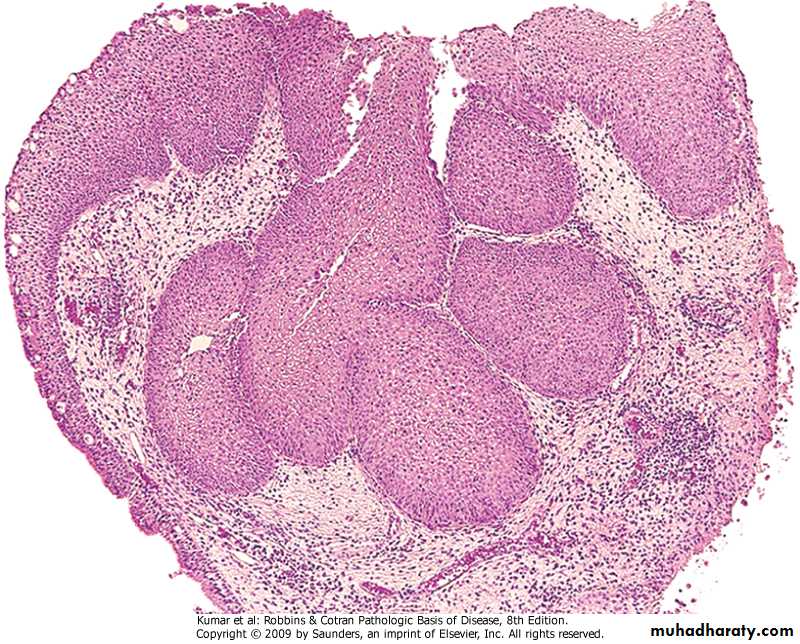

Silicotic nodules